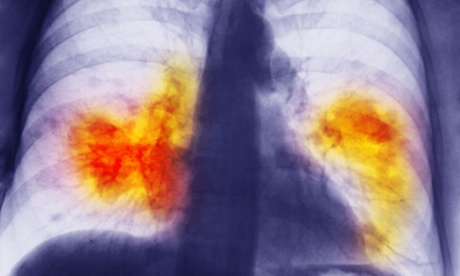

Chest x-ray showing lung cancer. In the 2000s, 18% of patients diagnosed with lung cancer in Austria survived – almost twice the rate in the UK.

One of the most stark examples was lung cancer, which only 7% of patients survived in the 1990s in the UK. The rate improved to 10% a decade later but this was still behind a 14% survival rate achieved in Austria in the 1990s. By the 2000s 18% of patients diagnosed with lung cancer in Austria survived – almost twice the rate in the UK.

Five other European countries (Finland, Germany, Italy, the Netherlands and Norway) also recorded better survival rates for lung cancer in the 1990s than Britain in the 2000s.